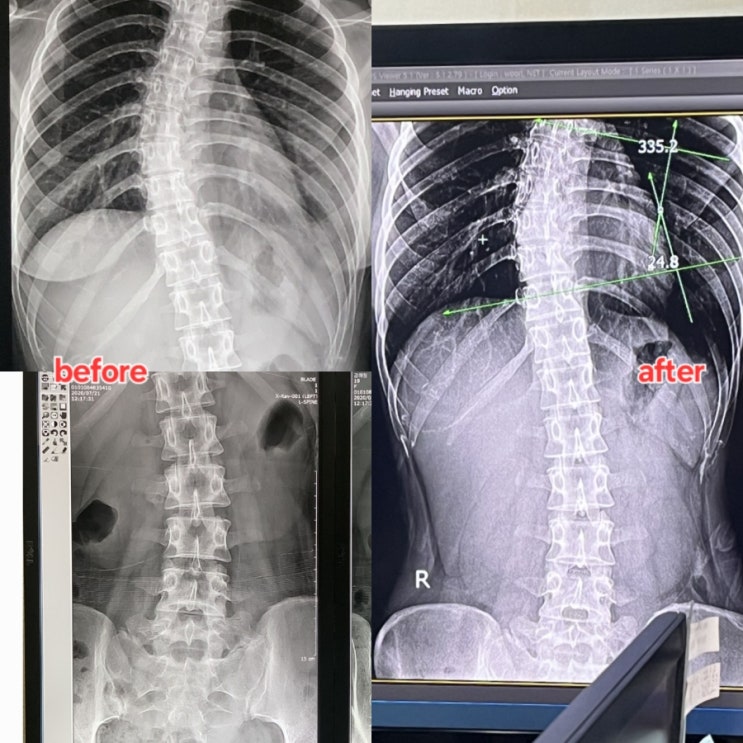

부산 시청역 필라테스 체형교정 비포에프터 모음

안녕하세요 라라(아라)입니다 오랜만에 본업모먼트로 포스팅을 해보려해요! 저는 경력 8년차의 필라테스 강...